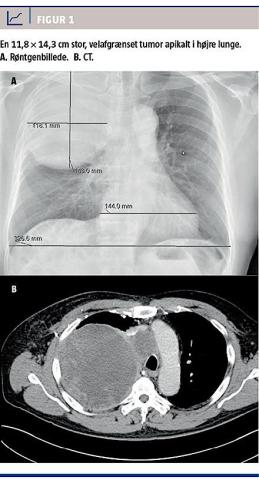

Objektivt fandt man, at han havde svækkede respirationslyde på højre side. Paraklinisk fandt man let forhøjet C-reaktivt protein, let leukocytose med overvægt af eosinofile granulocytter og normale levertal. Ved en CT blev der påvist en stor, velafgrænset, cystisk tumor med en inhomogen opladning apikalt i højre lunge (Figur 1). Desuden var der cystiske lymfeknuder i mediastinum samt cystiske processer i venstre binyre og nyrehilus. Med baggrund i skanningsfundene og hans rejseanamnese blev mistanken om infektion med Echinococcus rejst. Patienten blev testet for Echinococcus-antistoffer og var positiv for E. multicularis, men ikke for E. granulosus. Man påbegyndte behandling med albendazol og planlagde torakotomi med resektion af cysten.